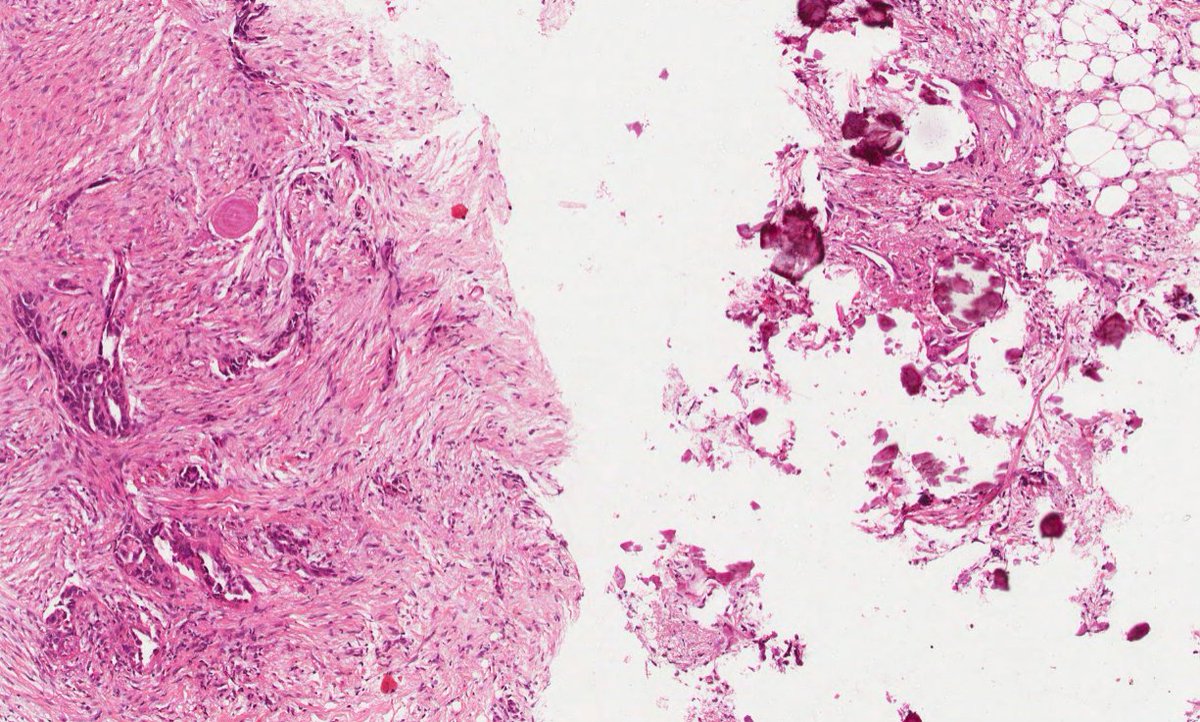

What neoplasm is causing this clavicular mass in a 65 year old man? View the whole slide on the Leeds Virtual Pathology Website here 🔬🔬🔬virtualpathology.leeds.ac.uk/slides/library… #softtissuepath #pathX #caseoftheweek